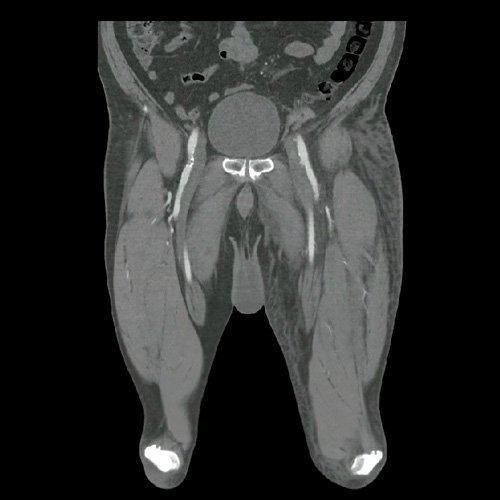

• AngioTAC de miembros inferiores (Día 2): Ateromatosis parietal calcificada parcheada en todo el territorio aorto-ilíaco-femoral bilateral. LADO DERECHO: Arteria ilíaca interna: de calibre y trayecto conservado, permeable. Arterias ilíaca externa y femoral común: de calibre y trayecto conservados, permeables. Arterias circunfleja ilíaca superficial y epigástrica superficial: de calibre y trayecto conservados, permeables. Arteria femoral superficial: de calibre y trayecto conservado, permeable. Arteria femoral profunda: de calibre y trayecto conservado, permeable. Arterias circunflejas femoral medial y lateral: de calibre y trayecto conservados, permeables. Arteria poplítea: de calibre y trayecto conservado, permeable. Arteria tibial anterior: de calibre y trayecto conservado, permeable. Arteria tibial posterior: de calibre y trayecto conservado, permeable. Vena ilíaca primitiva: 13 mm, vena ilíaca externa 11 mm, vena ilíaca interna 7 mm. LADO IZQUIERDO: En esta ocasión, en fase angiográfica se observa de calibre y opacificación conservada de las arterias femoral superficial y profunda, poplítea y de sus ramas musculares en muslo y pierna. En fase venosa se evidencia un defecto de relleno endoluminal de la vena primitiva izquierda que impresiona extenderse actualmente a la vena iliaca externa, a la vena femoral superficial y poplítea, hasta nivel del hueco homonimo, las cuales se visualizan aumentadas de calibre con respecto a sus contralaterales, en relación a trombosis venosa profunda. Se sugiere cotejar con ecodoppler de miembros inferiores. No se identifica compromiso de la porción visualizada de la vena cava inferior ni del sistema venoso ilíaco contralateral. Se visualiza dispositivo vascular en VCI (filtro VCI), infrayacente a las venas renales. Presenta aumento del diámetro del muslo izquierdo con respecto a su contralateral, asociado a edema de los tejidos blandos superficiales. Reticulación de la grasa de la región inguinal a predominio izquierdo con algunas burbujas aéreas. Se observa inmediatamente infrayacente a los antes mencionado, un área hiperdensa que realza en fase venosa, con centro hipodenso, que mide 2.2 cm x 1.4 cm, ya visualizado en tomografía previa. Cambios artrodegenerativos coxo-femorales y tricompartimentales en la rodilla. Signos de entesopatía cuadricipital distal. No se observan alteraciones a nivel del fémur ni de las porciones visualizadas de la tibia y el peroné. Arteria ilíaca interna: de calibre y trayecto conservado, permeable. Arterias ilíaca externa y femoral común: de calibre y trayecto conservados, permeables. Arterias circunfleja ilíaca superficial y epigástrica superficial: de calibre y trayecto conservados, permeables. Arteria femoral superficial: de calibre y trayecto conservado, permeable. Arteria femoral profunda: de calibre y trayecto conservado, permeable. Arterias circunflejas femoral medial y lateral: de calibre y trayecto conservados, permeables. Arteria poplítea, tibial anterior y tibial posterior: de calibre disminuido con respecto a su contralateral, permeables. Vena ilíaca primitiva: 14 mm, vena ilíaca externa 17 mm, vena ilíaca interna 9 mm. Calcificaciones en conducto inguinal bilateral. Hidrocele bilateral.

• Flebotomografia de miembros inferiores (Día 18): Filtro de vena cava inferior infrayacente a venas renales. Stent metálico a nivel de la vena ilíaca común y externa izquierda, permeable. Se explora la región venosa del territorio femoral y poplíteo, evidenciándose defectos parciales de relleno endoluminal a nivel de la vena femoral superficial y profunda izquierdas, compatibles con trombosis venosa parcial. A nivel del tercio distal de la vena femoral común izquierda, se evidencia aumento de calibre e interrupción brusca de la opacificación del contraste (“signo de stop”), compatible con trombosis venosa oclusiva en dicho nivel, sin opacificación venosa distal. Se observan similares hallazgos a nivel de la vena femoral superficial contralateral, evidenciándose defectos de relleno endoluminal parcial hasta su tercio distal, con ausencia de opacificación distal. Salvo mejor criterio sugiero complementar con eco-Doppler de venoso de ambos miembros inferiores. Presenta edema difuso de los tejidos blandos de miembro inferior izquierdo. Se observa en los tejidos blandos de la región inguinal izquierda, colección hipodensa con realce periférico que mide 4.7 cm AP x 4 cm. Además se observan ganglios locorregionales aumentados en número y tamaño, algunos de rango megálico.

Angio TAC de miembros inferiores (Día 2)